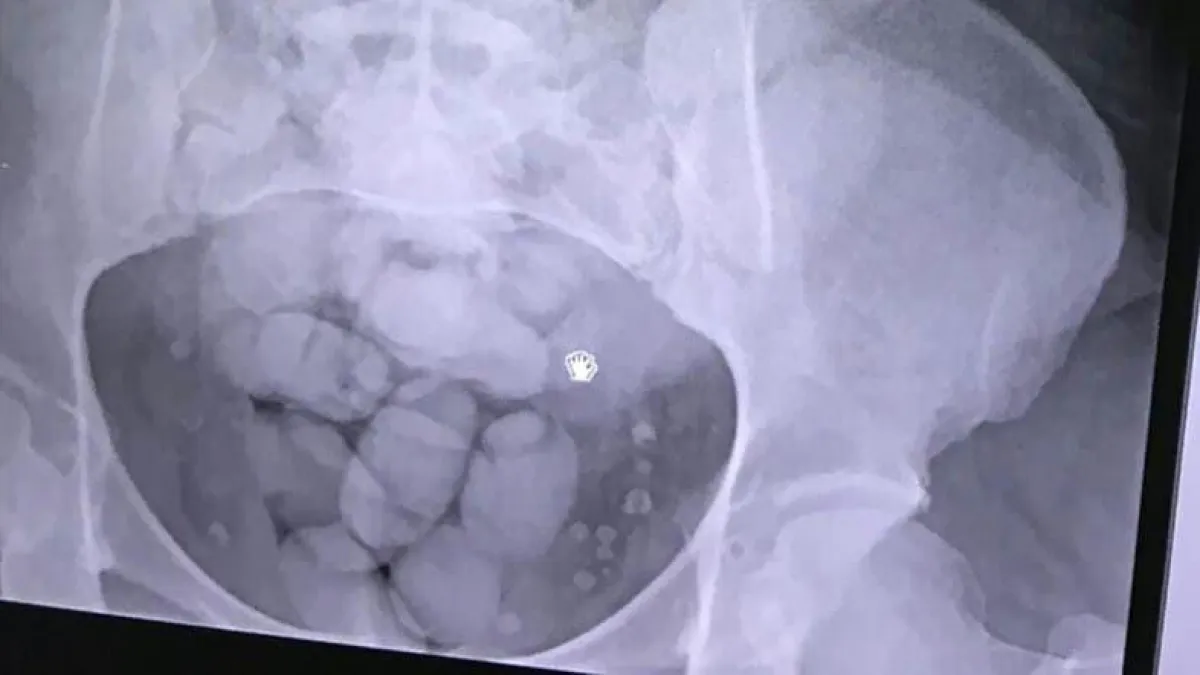

وتابعت الصحيفة اليابانية أن السلطات المكسيكية كانت قد أكدت بأن الراكب كان قد لقي حتفه على متن تلك الرحلة، جراء إصابته بـ«وذمة دماغية» بسبب تعاطيه جرعات زائدة من المخدرات. ومن جهتها أشارت النيابة العامة في ولاية «سونورا»، إلى أن الراكب الياباني كان قد ابتلع 246 كيساً من الـ«كوكايين»، كل كيس يبلغ طوله 2.5 سنتيمتراً، وعرضه سنتيمتراً واحداً، مؤكدة بأنه تم العثور عليها جميعها في معدته وأمعائه عند تشريح الجثة.